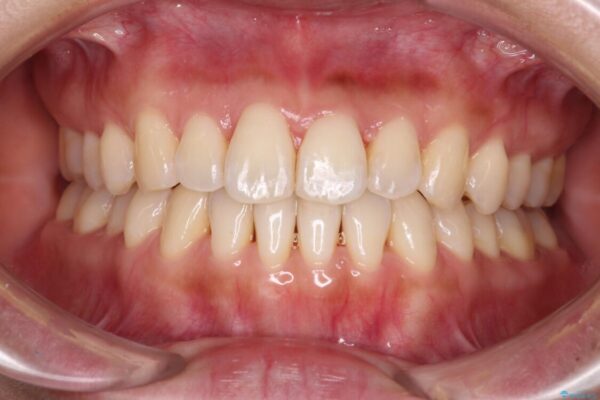

治療後

• 【モニター】前歯のデコボコをインビザラインで改善 治療後画像